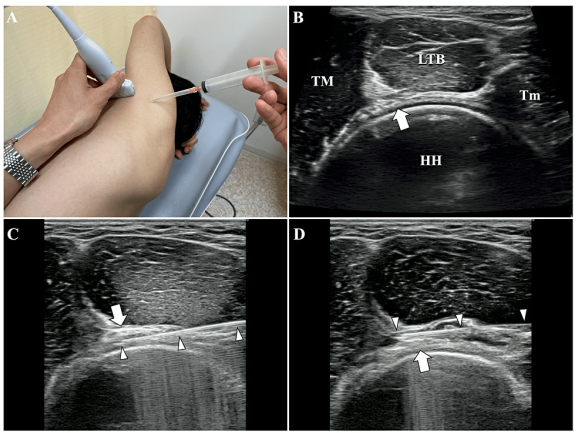

DOI: 10.7759/cureus.60157 1. 흉배신경 (TDN) 치료: 환자는 눕거나 엎드린 자세에서 진행됩니다. 광배근(LD), 대원근(TM), 견갑하근(SSC) 사이를 지나는 흉배동맥을 이정표(landmark) 삼아 신경 다발을 찾아냅니다. 이곳에 약침을 정밀하게 주입하여, 신경과 주변 유착된 조직 사이를 부드럽게 분리시키고요.  2. 액와신경 (AxN) 치료: 다음은 옆으로 누운 자세에서 액와신경을 찾습니다. 액와동맥을 이정표 삼아 상완골두(HH), 대원근(TM), 소원근(Tm), 상완삼두근 장두(LTB)로 형성된 곳을 지나는 액와신경 다발을 확인합니다. 역시 초음파로 실시간 확인하면서 신경과 주변 조직을 떼어놓습니다. 이러한 치료는 유착된 신경의 움직임과 기능을 개선하고, 신경 주변의 국소 혈액 순환을 증진시켜서 신경에서 오는 통증을 완화하는 데 효과적입니다. > 결과는? > > 관절와순 파열 관절염 어깨 통증 치료 흉배신경에 시술 직후, 앞서 양성이었던 CAT 검사가 정상이 되었고, 액와신경 시술 직후에는 HFT 검사 역시 호전되었습니다. *즉각적으로

2. 액와신경 (AxN) 치료: 다음은 옆으로 누운 자세에서 액와신경을 찾습니다. 액와동맥을 이정표 삼아 상완골두(HH), 대원근(TM), 소원근(Tm), 상완삼두근 장두(LTB)로 형성된 곳을 지나는 액와신경 다발을 확인합니다. 역시 초음파로 실시간 확인하면서 신경과 주변 조직을 떼어놓습니다. 이러한 치료는 유착된 신경의 움직임과 기능을 개선하고, 신경 주변의 국소 혈액 순환을 증진시켜서 신경에서 오는 통증을 완화하는 데 효과적입니다. > 결과는? > > 관절와순 파열 관절염 어깨 통증 치료 흉배신경에 시술 직후, 앞서 양성이었던 CAT 검사가 정상이 되었고, 액와신경 시술 직후에는 HFT 검사 역시 호전되었습니다. *즉각적으로